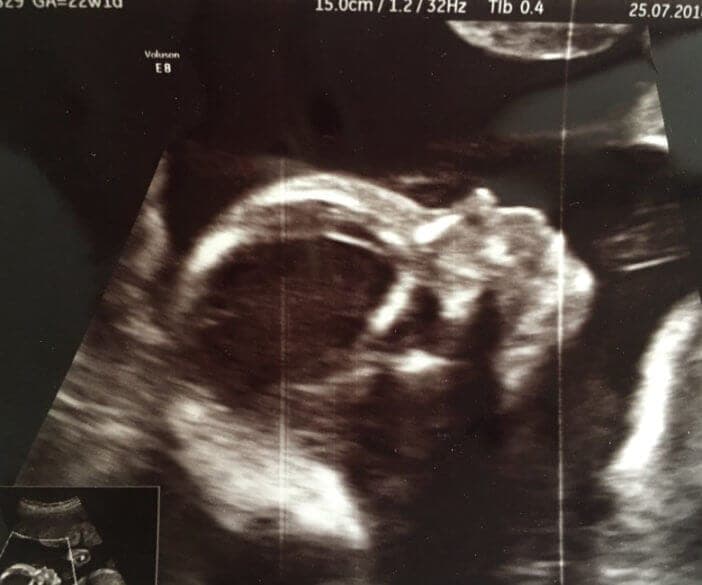

Unser Besuch beim FrauenarztWir hatten am 25.07 unseren zweiten großen Ultraschall-Termin und haben uns für den erweiterten Basis-Ultraschall entschieden. Die Untersuchung haben wir auf Video aufgenommen:

Zum Glück scheint mit unserem Baby alles in Ordnung zu sein. Ich finde den Ultraschall immer wieder faszinierend! Wenn es oft so irreal ist, dass da ein Baby in meinem Bauch lebt, dann wird es in diesen Momenten so greifbar. Mittlerweile erkennt man auch das Gesicht schon sehr gut, sieht wie sich die kleinen Arme und Beinchen bewegen und es ist einfach unbeschreiblich. Ich freue mich dann immer so sehr auf den Moment, in dem wir den kleinen November-Jungen endlich im Arm halten können.